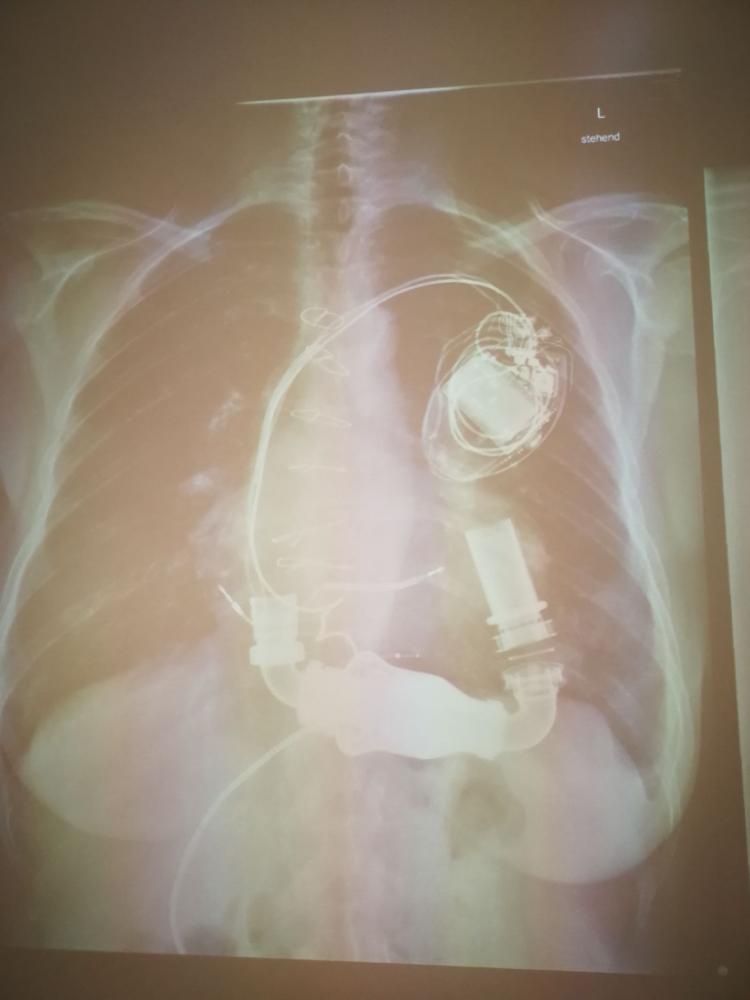

Der spannendste Teil seines Besuchs war die Vorstellung von „Kunstherzen“. Dr. Höfer hatte verschiedene Modelle von pulsierenden Unterstützungssystemen dabei, die Patienten mit schwerer Herzschwäche unterstützen oder sogar das Herz vollständig ersetzen können. Er erklärte, dass solche Kunstherzen oft als Übergangslösung bis zu einer Herztransplantation genutzt werden. Zudem gab er uns eine Demonstration eines solchen Kunstherzens mit der Hilfe von Wasser, welches Blut darstellen sollte. Ein besonderes Highlight war ein echtes Operationsvideo, das zeigte, wie ein Kunstherz chirurgisch eingesetzt wird. Es war beeindruckend zu sehen, wie präzise Chirurgen arbeiten müssen, um ein Leben zu retten.